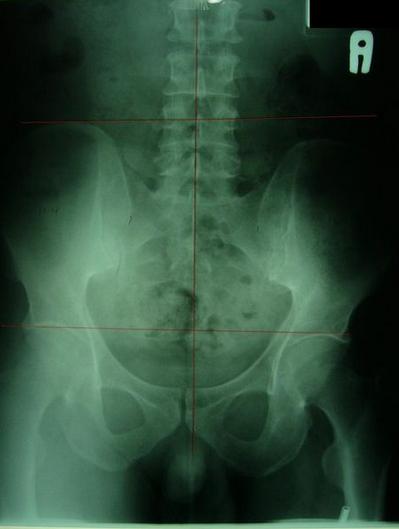

案例A:右骨盆明显较低中线未穿过耻骨联合

一般最常见到骨盆歪斜的案例包括产后骨盆不正、车祸、撞击、跌倒、姿势不良…等等造成。骨盆歪斜的典型症状包括腰部、髋臀部、腿、膝部疼痛。列举三个自在美国取得脊医执照以来曾经处理过骨盆歪斜相当明显的案例。都是骨盆部位曾经遭受撞击。案例A是超过十年以上的陈年车祸旧伤、另一案例B是急性摔伤(两天内)的案例。两者的X光片都依照美国脊医X摄影方式采站姿摄影评价。借此同时评价骨盆在重力(gravity)影响下的反应。也可以泯除躺歪斜摄影而造成图像不正的情况。最简单的评价要点包括骨盆高低边?中线是否穿越耻骨联合?左右两边是否对称?我简单的几条线一画,相信连外行人也可以看出明显的骨盆歪斜的情况。案例A属陈旧性伤害在调理约两个月后明显降低腰臀腿部的不舒服。而案例B属急性伤害,案例B在调理近三周后骨盆疼痛由原先的持续疼痛降低为完全不痛。之后的骨盆X光摄影重新评价也显示骨盆旋转的问题大幅改善。